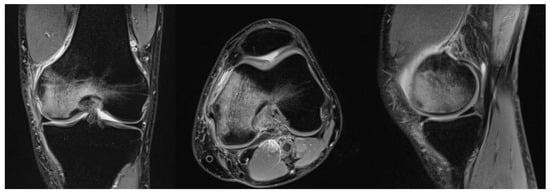

Because of its inherently high sensitivity, MRI is useful in the early stages of both SPONK and secondary ON. As bone oedema is presented from the early onset of the disease, these features are picked up on the MRI with high accuracy. On T1 images, features suggestive of osteonecrosis are low signal changes in the subchondral area in the affected condyle []. Typically, a crescentic fracture line may/can appear (in the images). These appearances were initially described in the hip and have now been identified and studied in osteonecrosis of the knee []. On T2-weighted images, the affected area has a margin of high signal changes [] (Figure 1).

Figure 1.

MRI of a right knee in a 51-year-old man showing osteonecrosis of the femoral condyle.